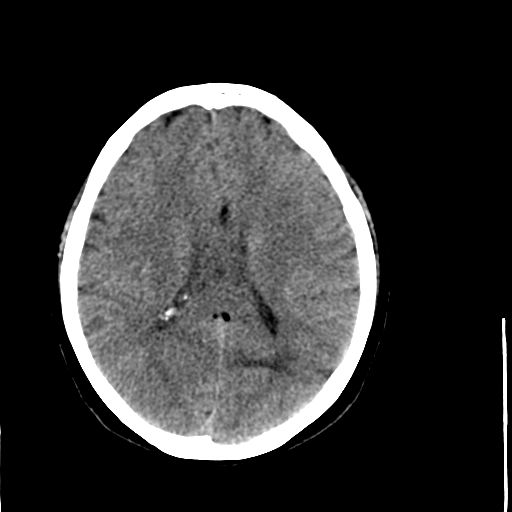

病人资料:女,57岁,反复头痛6年余,无恶心、呕吐等症状,体查:bp180/100mmhg。

胼胝体发育不良并脂肪瘤形成,脂肪瘤形成是因,胼胝体发育不良是果。如果正规些应该是中线脂肪瘤并胼胝体发育不良!

典型中线脂肪瘤

胼胝体发育不良

中线脂肪瘤并胼胝体发育不良。